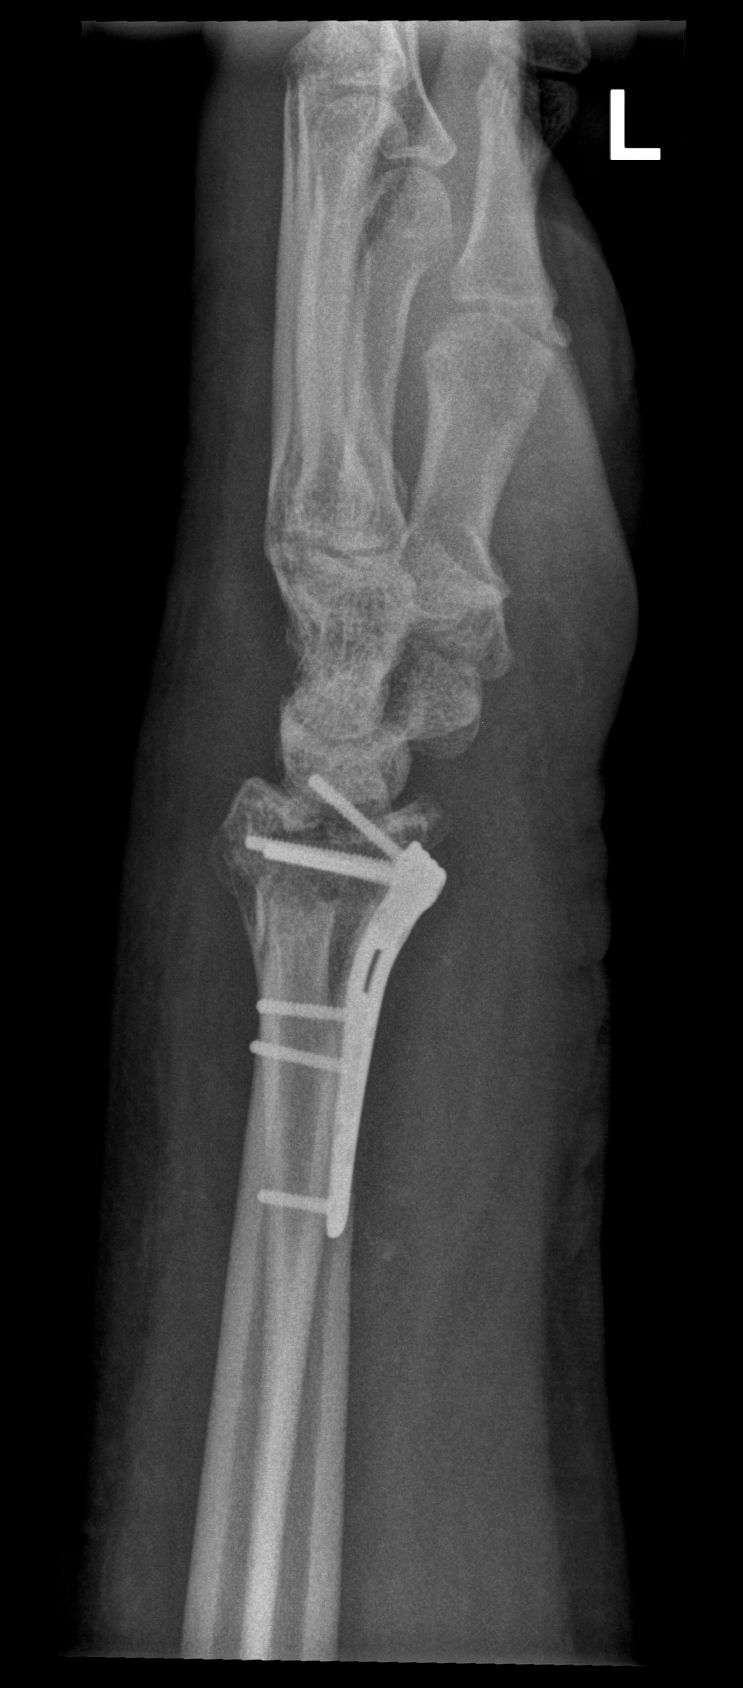

Successful surgery to reduce and fixate with the plate of neglected, displaced fracture of the distal radius

Treatment of neglected, displaced or united distal radial fractures (DRFs) is difficult, because it requires either wedging the almost consolidated fracture and reduction to the correct position, or cutting the united bone and putting it in the correct position (corrective osteotomy). Both treatments are associated with the risk of failure and complications. The paper presents a case of almost fully united DRF in a man, in whom 5 weeks after the injury, and after unsuccessful primary fixation with K-wires, the bone fragments were surgically wedged, aligned and fixed with a palmar plate. The result of treatment after 2 months was satisfactory. Early surgery allowed for a significant shortening of the recovery period and allowed the patient to return to work.